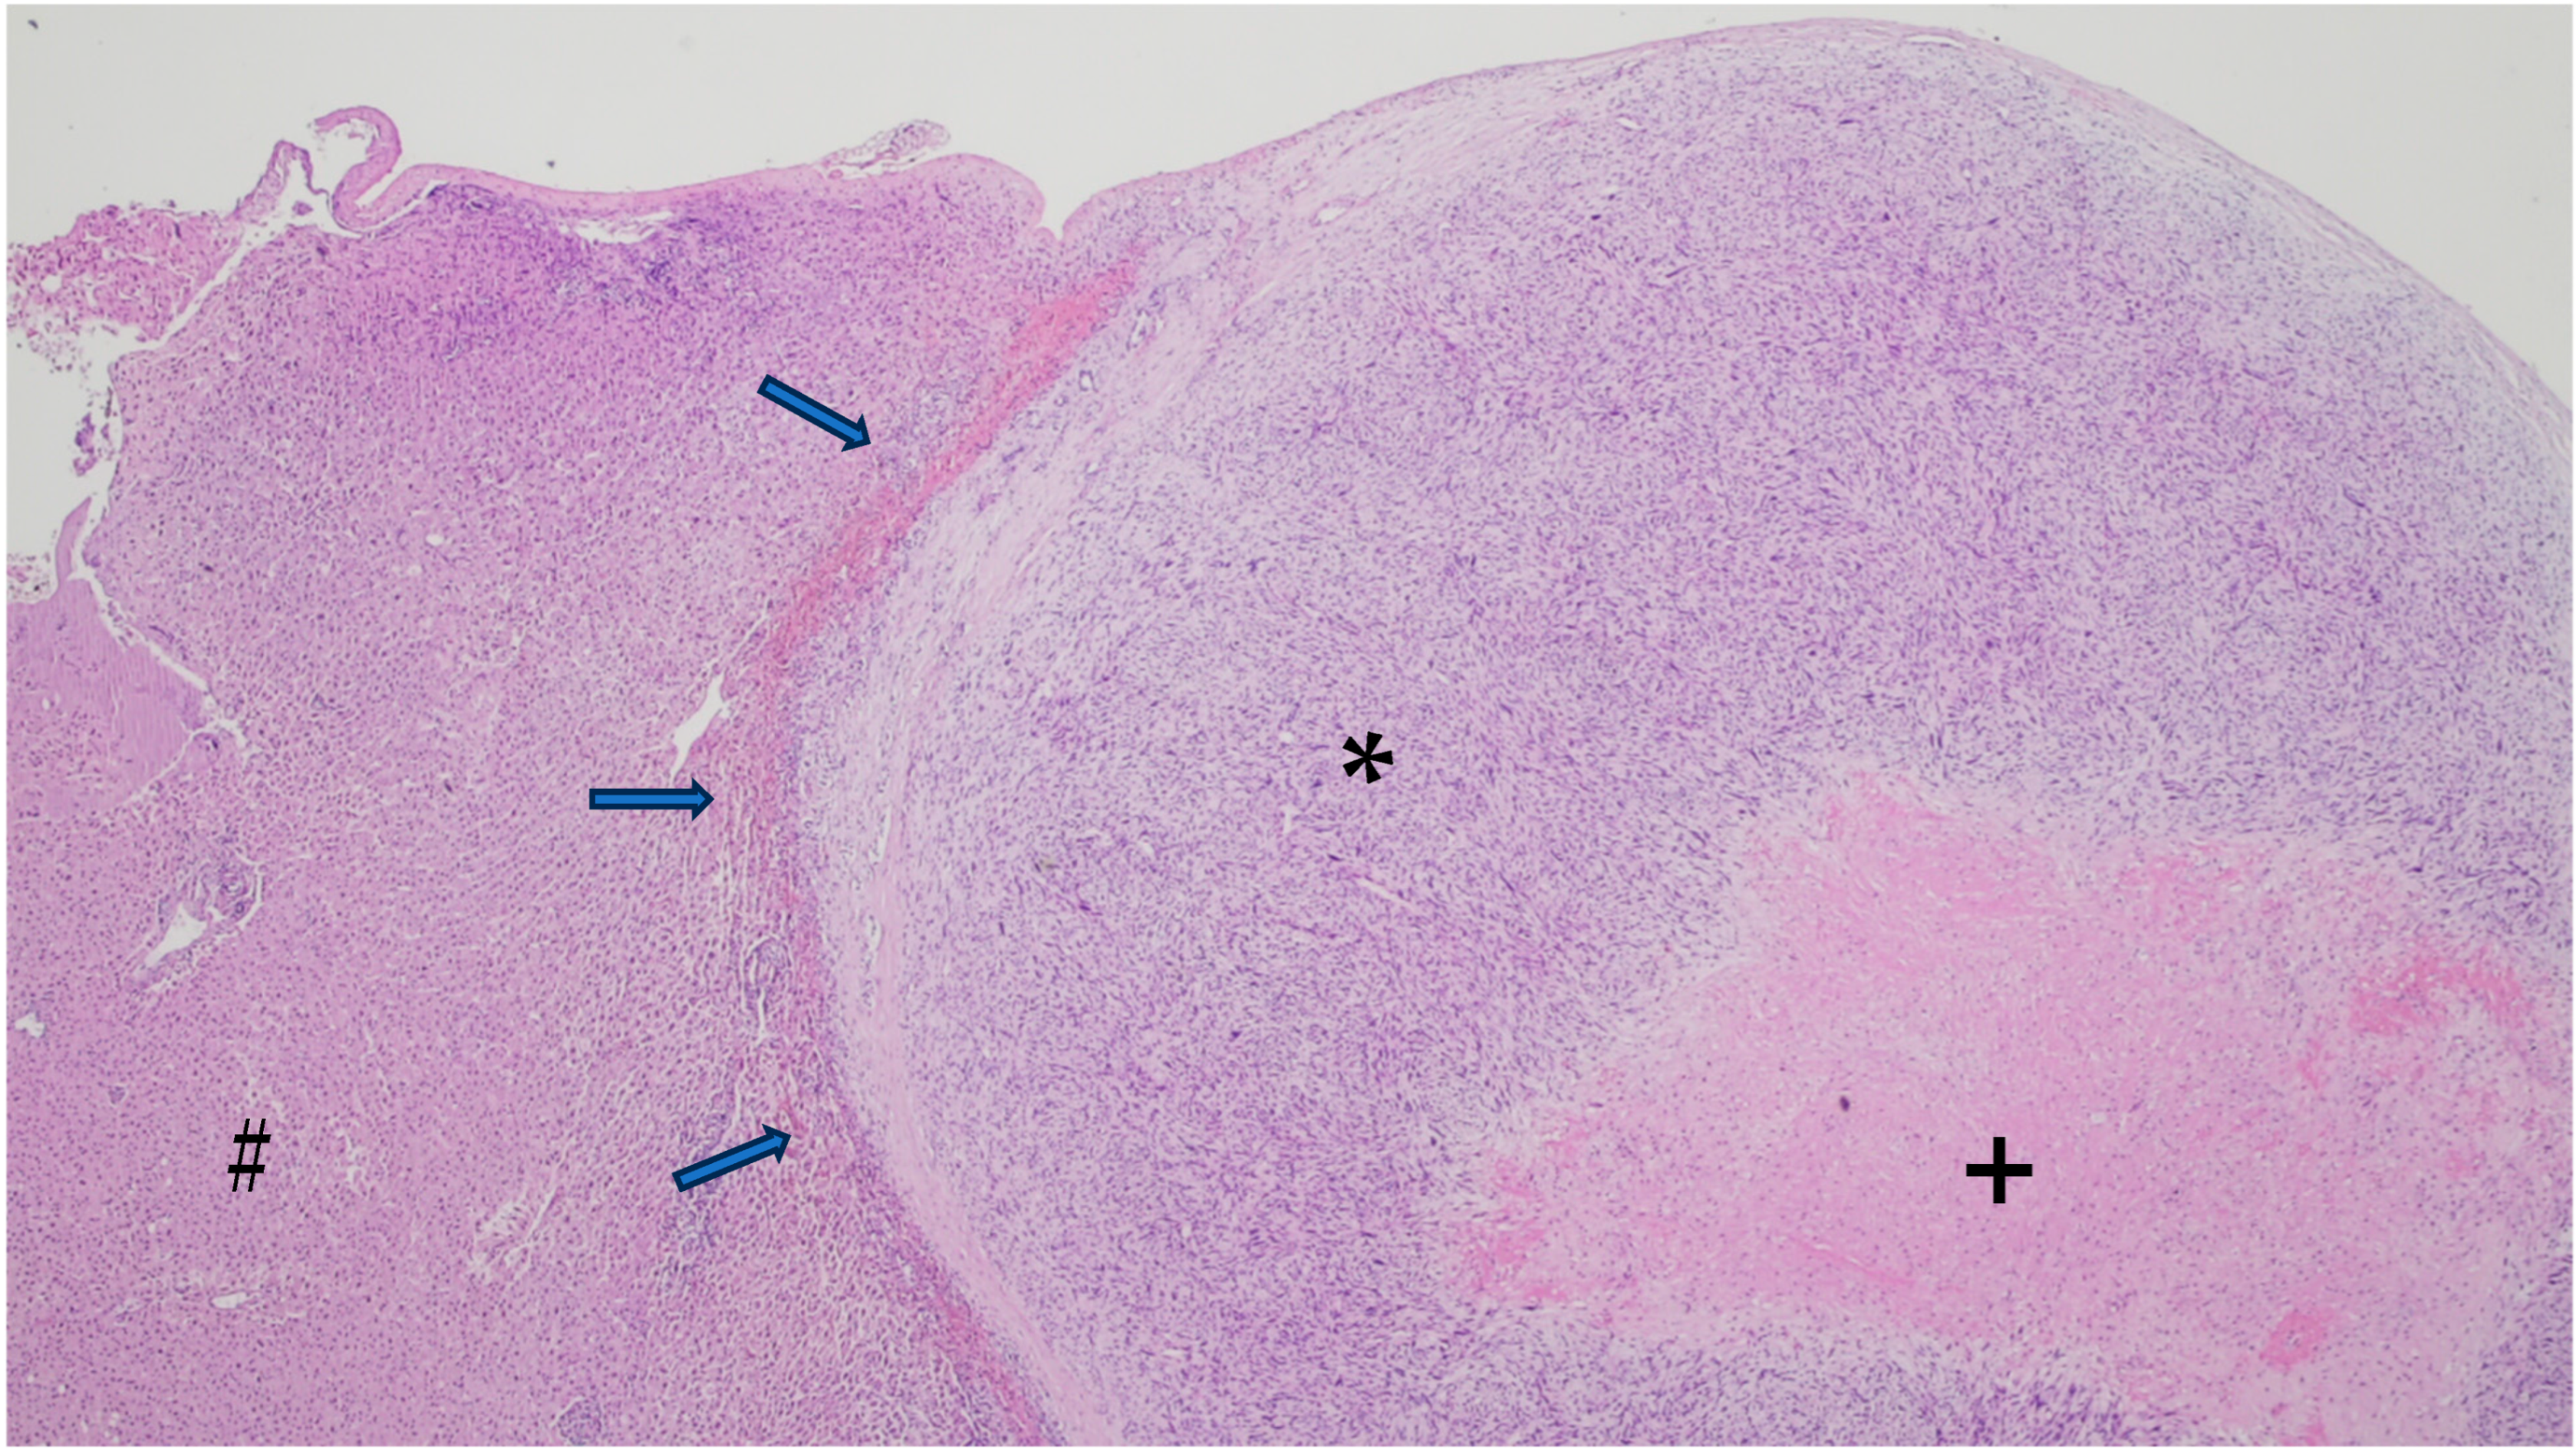

6. Gross and Histologic Features